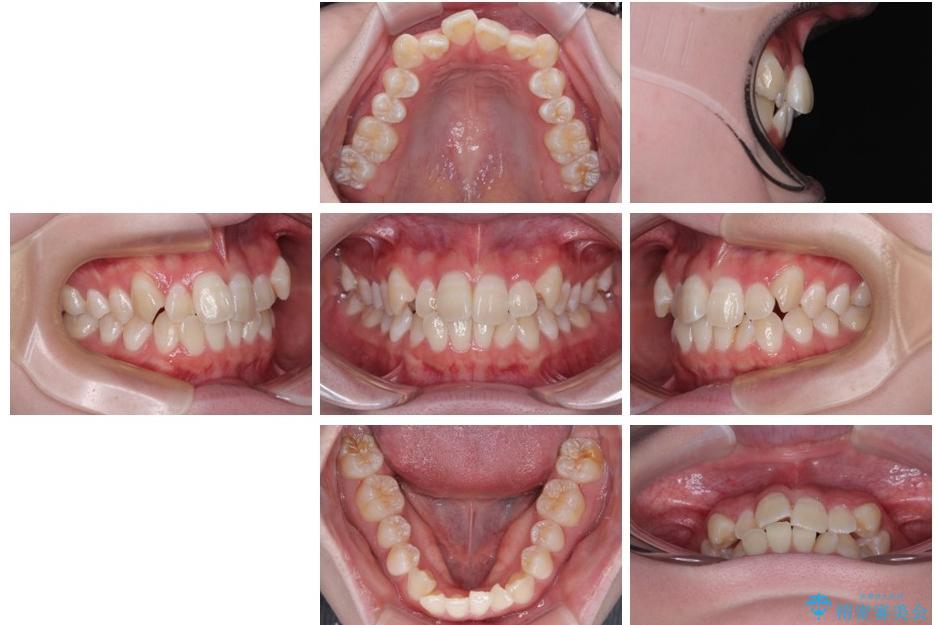

治療前

• 【モニター】前歯のデコボコをスッキリ解消!目立ちにくいワイヤー矯正でスピーディに治療完了 治療前画像

「前歯のデコボコ(叢生)をきれいに整えたい」とのことでご来院されました。